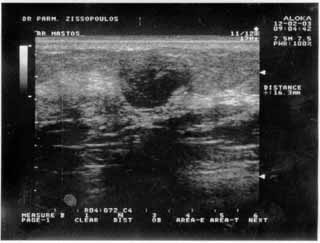

Oι τελευταίες 4 απεικονίσεις έγιναν με ειδικό για μαστό ηχοβολέα linear, εναλλασσομένης συχνότητος 7,5-10ΜΗΖ.

Δρ Παρμενίων Ζησόπουλος

Μαιευτήρας- Χειρούργος Γυναικολόγος